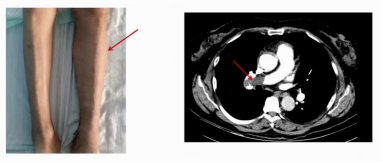

患者出现BNP、D-D二聚体逐渐升高,左下肢水肿加重;复查双下肢深静脉超声提示右下肢深静脉血栓形成,肺动脉CTA结果显示肺动脉栓塞。将低分子肝素加量至治疗量100IU/kg,每12小时一次;经一段时间治疗后,患者成功撤机。